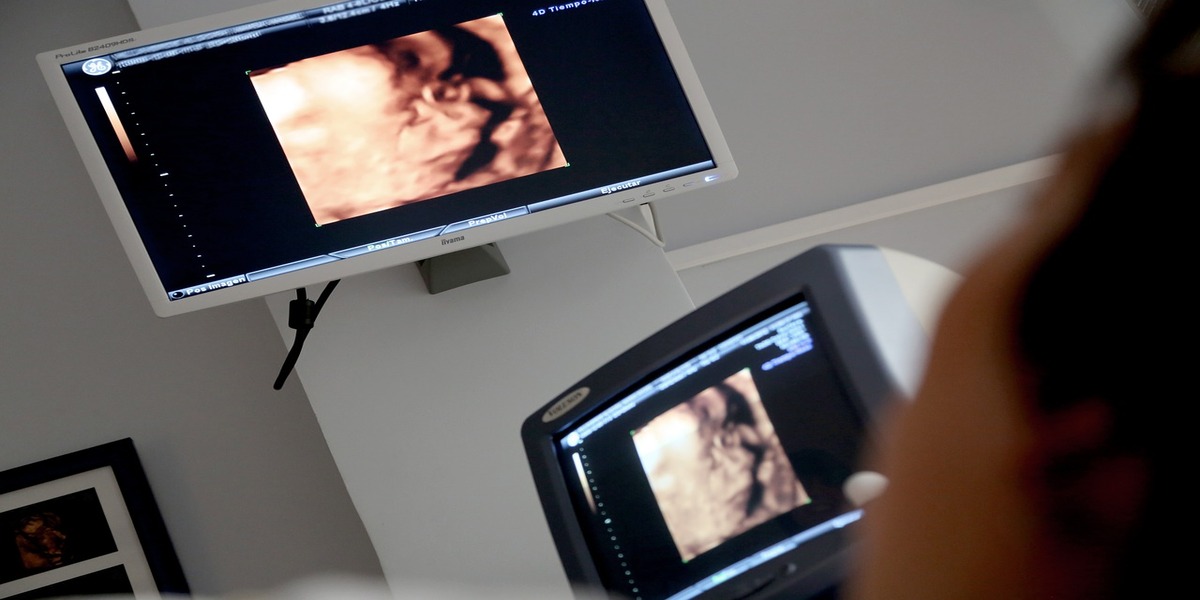

L’ecografia è un esame diagnostico che utilizza gli ultrasuoni per ottenere immagini degli organi interni del corpo. E’ uno degli strumenti più utilizzati nei più svariati ambiti clinici, in quanto considerato esame di primo livello, cioè il primo a cui viene sottoposto un individuo nel sospetto di una qualche patologia.

Non è assolutamente un esame di tipo invasivo, poiché l’ecografia non utilizza radiazioni ionizzanti, infatti è totalmente innocuo ed è anche consigliato per monitorare il feto delle donne in gravidanza.

L’utilità è diversa e in molti campi della medicina, ad esempio per la prevenzione e la diagnosi dei tumori, per indagare su ogni possibile degenerazione dei tessuti e organi. Inoltre l’ecografia viene utilizzata per indagare sullo stato di tendini e muscoli, quindi al fine di identificare infiammazioni o degenerazioni di tendini o lesioni muscolari.